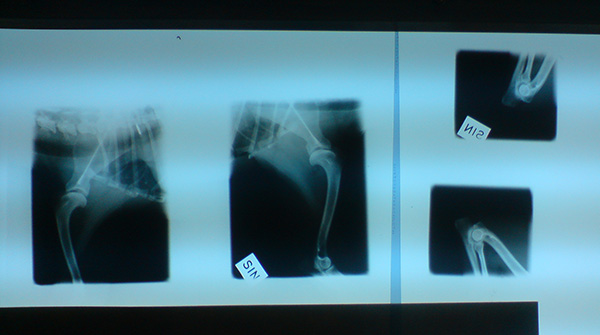

Bosse kollade igenom Piraya och hittade absolut ingenting. Ingen hälta eller ömmande vid palpering. Han menade att om jag kommit till honom utan remiss från sjukgymnasten hade han inte kunnat utröna något överhuvudtaget, särskilt som hon inte uppvisat några som helst symptom den sista tiden på t ex smärta, orolighet etc. Självklart blev det ändå en tur in på röntgen för att se om benen visade något annorlunda. När plåtarna kom visade de att Piraya har kanonfina bogar och armbågar! Inga förändringar eller pålagringar what so ever! Härligt!! Bosse menade på att hon borde uppvisa mycket högre symptom om det skulle varit artros, så nu är det helt struket. Som sagt, helt onödigt av mig att bli uppjagad efter första ”domen”, men det kändes verkligen piss i måndags och tisdags.